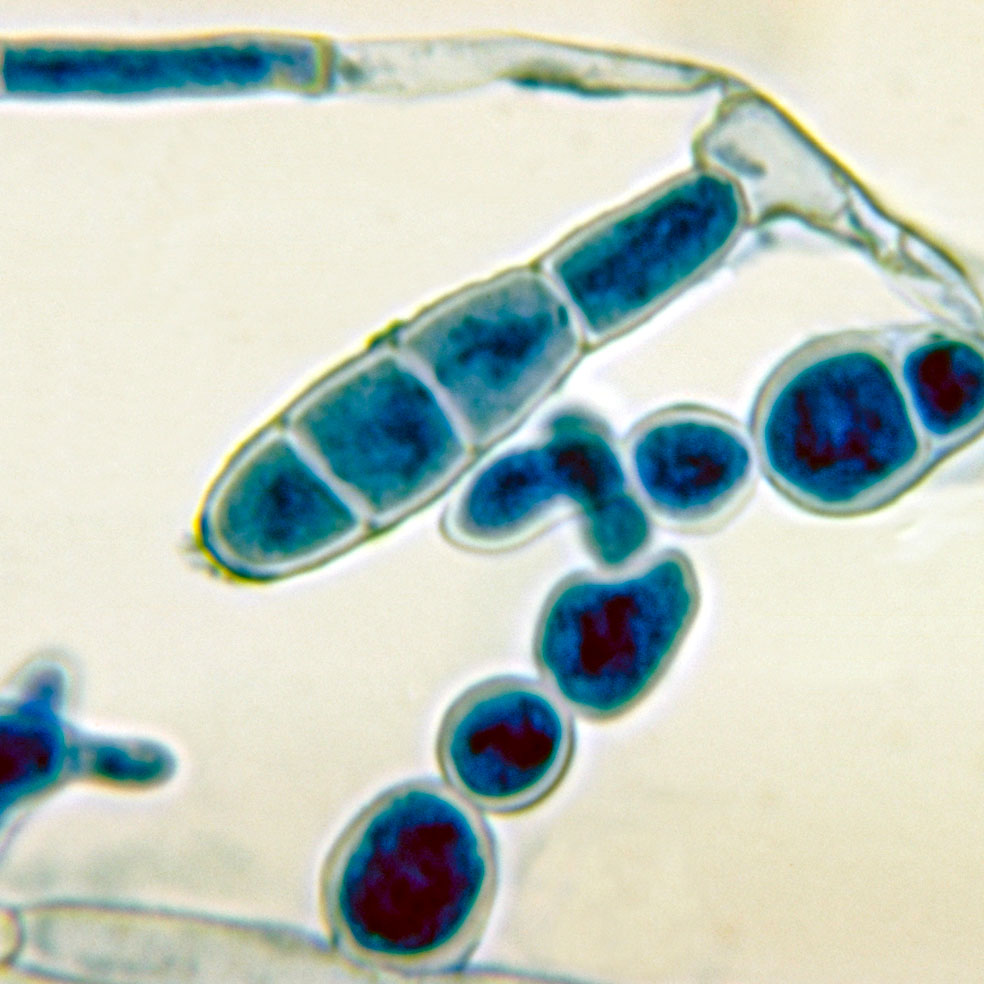

El origen se halla en tres tipos de hongos: Microsporum, Epidermophyton y Trichophyton, criaturas milenarias que invaden las capas superficiales de la piel, el pelo y las uñas. Es donde encuentran alimento y se reproducen. Por eso una vez ahí se multiplican, generando una erupción cutánea redondeada que se deshace en escamas y causa picor. Si no se trata a tiempo, puede provocar dolor, fiebre, caída del cabello e, incluso, alopecia en las zonas afectadas. Su capacidad de transmisión es muy elevada: basta tocar a una persona infectada u objetos contaminados como las máquinas en cuestión, peines, ropa, suelo de duchas, piscinas...

Trichophyton y Epidermophyton son dos géneros de hongos que se pegan a los pies en las duchas públicas, ocasionando una infección conocida como tiña podal o pie de atleta. Estos microorganismos proliferan en zonas cálidas y húmedas, por lo que se recomienda tener los pies limpios y secos, sobre todo entre los dedos.